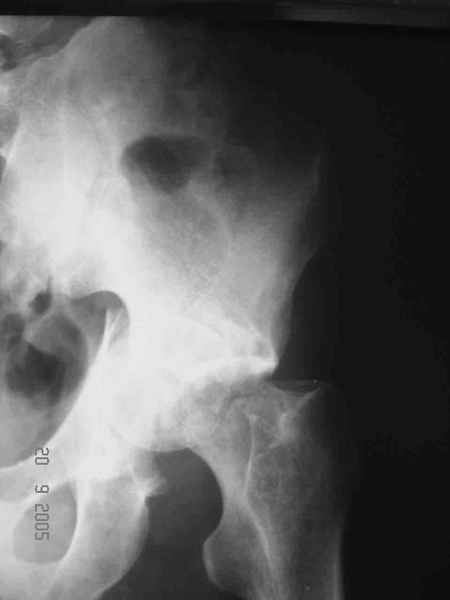

Больной 18 мая 2003 года в автоаварии получил перелом левой вертлужной впадины, вывих бедра. Госпитализирован в один из стационаров области.Вывих вправлен. В последствии бедро вывихивалось еще дважды. На консультацию был представлен снимок от 19.05.03г., больной переведен к нам 3.06.03г. Снимок при поступлении - перелом впадины, задне-верхний вывих бедра. 05.06.2003 г. выполнено открытое вправление вывиха левого бедра и остеосинтез стенки вертлужной впадины двумя винтами. Послеоперационный период без осложнений. Объем движений в левом тазобедренном суставе восстановился полностью. Выписан на амбулаторное лечение в удовлетворительном состоянии с рекомендациями 3 месяца ходить на костылях без нагрузки на оперированную конечность. На контрольных рентгенограммах левого тазобедренного сустава 13.10.2003 г. - признаки консолидации перелома; плотность, форма головки и состояние суставных поверхностей удовлетворительные. Разрешена дозированная осевая нагрузка, на конечность с использованием дополнительной опоры. 19.12.2003 г. больной обратился с жалобами на боли в левом тазобедренном суставе. На рентгенограммах левого тазобедренного сустава 19.12.2003 г., 20.02.04г. - асептичекий некроз головки бедра. 5.04.04г. - эндопротез. Сейчас ходит без трости, не хромает. Особенность эндопротезирования - при удалении винтов прослежена линия перелома заднего края впадины и предложено установить чашку несколько меньшего диаметра, чтобы она была покрыта несломанной частью.

Послеоперационный снимок прямой 5/05/03

|

Послеоперационный снимок боковой 5/06/03